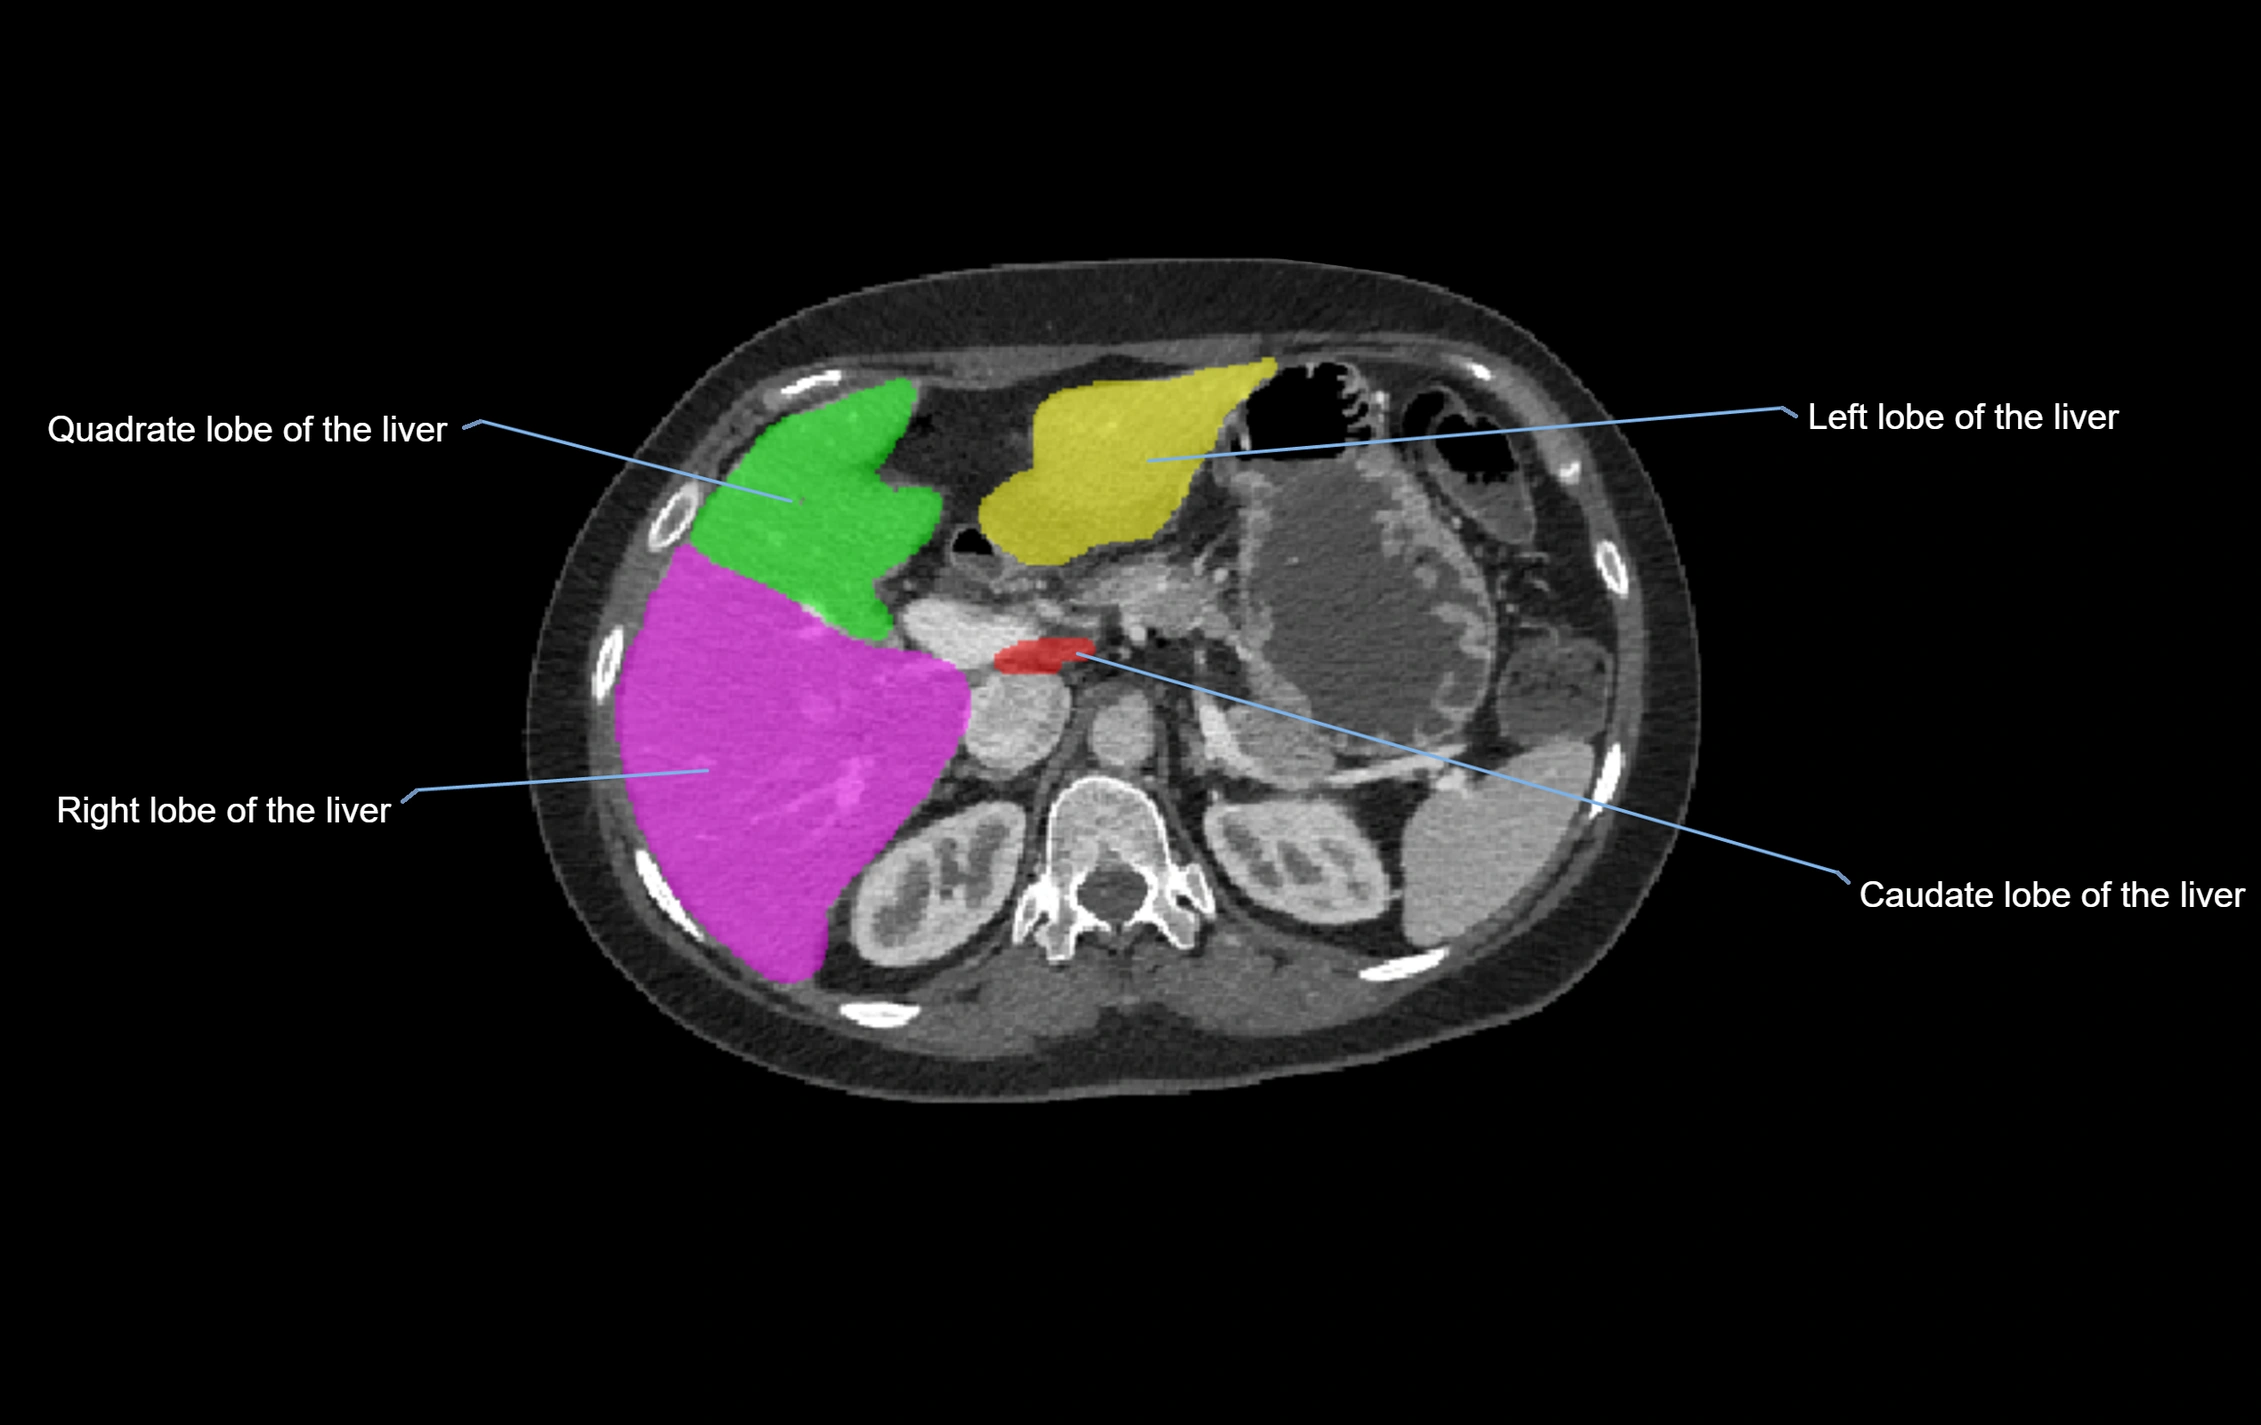

CT Image

image